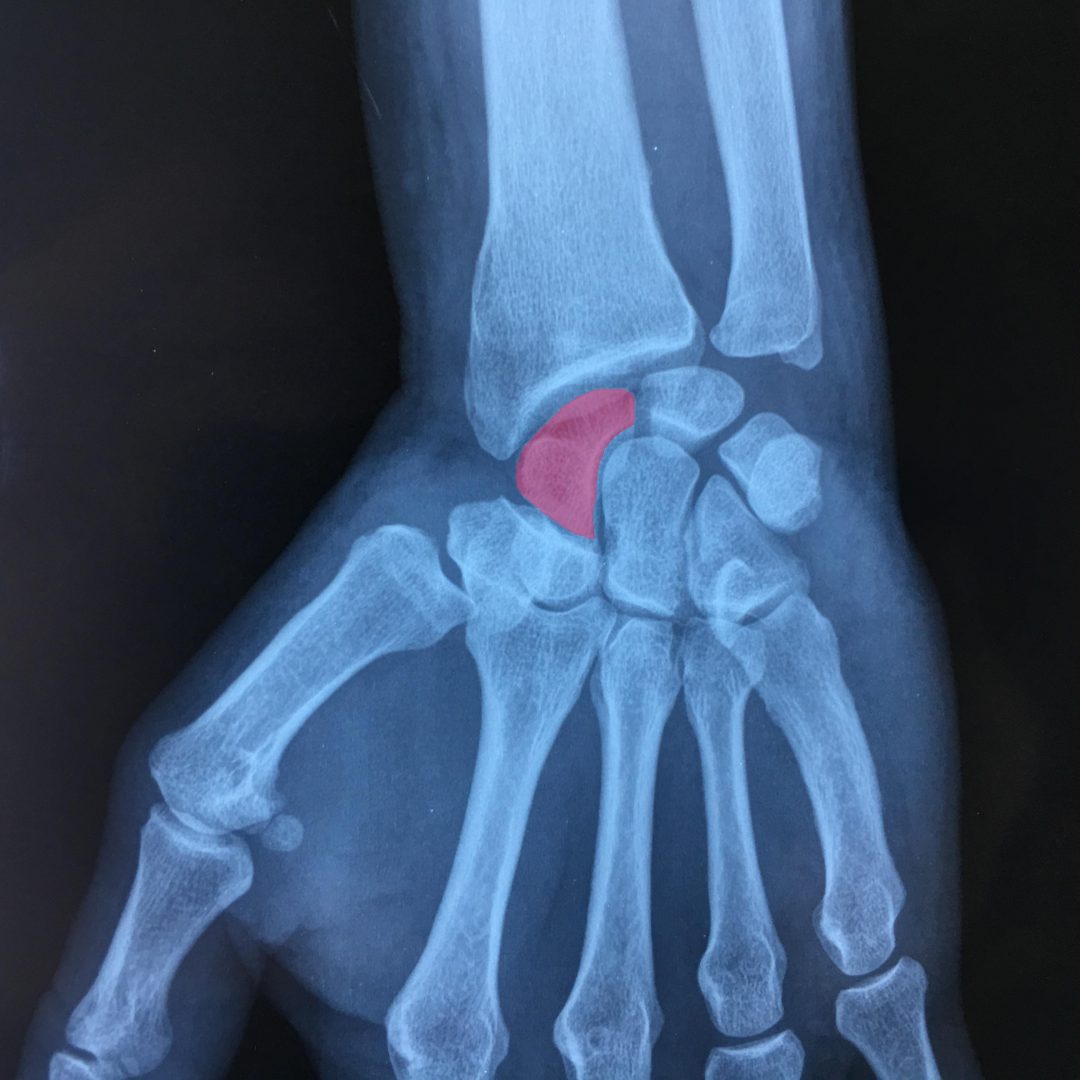

Ce qui se passe La main est constituée en partant du poignet : Du carpe constitué de 8 os solidement reliés par des ligaments Les fractures carpiennes courantes comprennent celles du scaphoïde et de l'os hamatum (voir Traumatismes. Les fractures de la main comprennent les suivantes : Fractures des os du poignet (carpes)